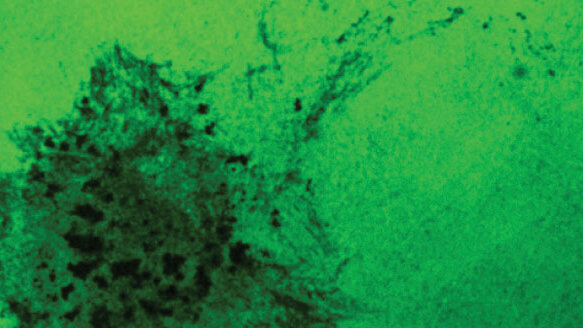

Ultimately, the researchers found, the immune-response loop resulted in increased invasive structures known as “invadapodia,” used by the cancer cells to invade and metastasize.